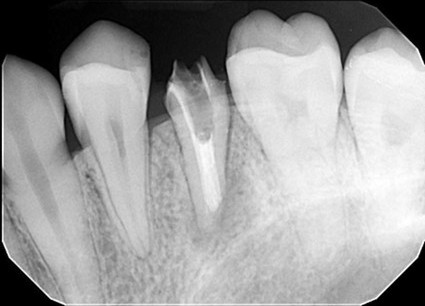

| 主訴 | 歯がしみる・見た目を改善したい |

| 状態 | 完全に神経が見えている状態だったので、根管治療を行ったのちセラミックで審美回復した症例。 |

| 料金 | 根管治療9万円+税、ファイバーコア2万円+税、仮歯1.5万円、E=MAXクラウン11.5万円+税(1本)×2本分=48万円 |

※根管治療と審美は別っていう医院が多いけど、包括的に治療できることが強み